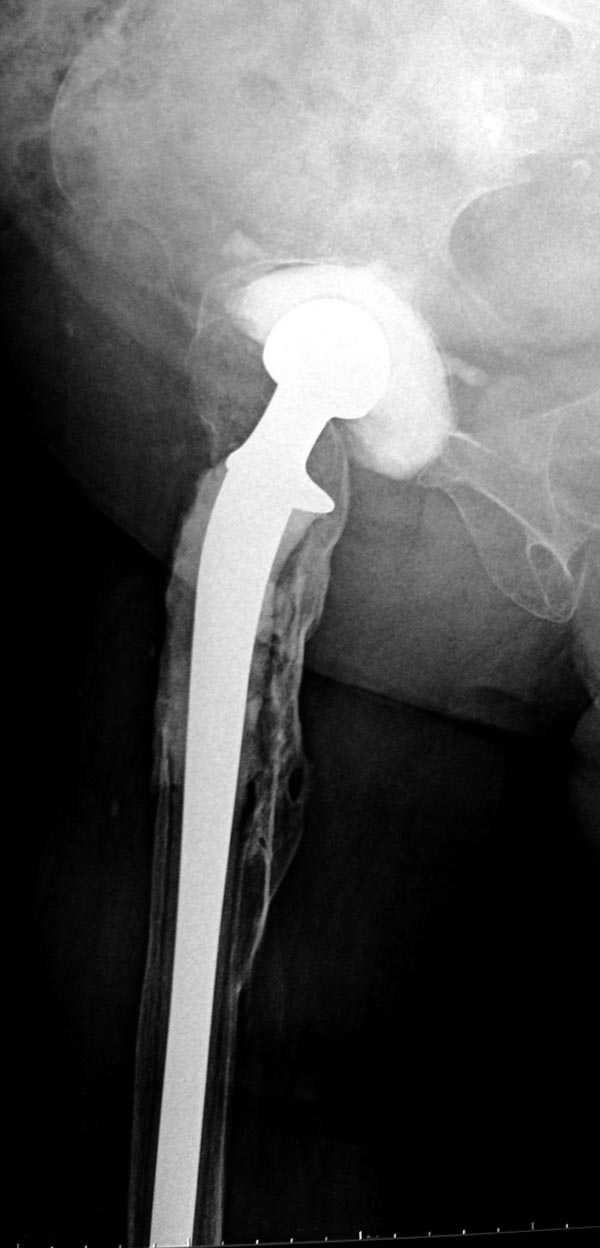

Из предложенных вариантов быстрейший результат можно ожидать после поэтапного эндопротезирования.

"Антибиотико-цементные" спейсеры после купирования

инфекции уже после первого этапа позволяют больным

передвигаться самостоятельно, иногда нагружая конечность годами.

Как-то показывал случай после осложненного тотального эндопротеза, сперва из-за отсутствия экономических возможности, а затем привыкшая к своей участи вот уже более 8 лет ходит на временном "протезе-спейсере".

Полость вертлужной впадины и проксимальное бедро были заполнены custom made временным протезом из цемента.

Для бедренного компонента можно применить старую

длинную ножку протеза и желательно малого диаметра.

Цементная смесь наносится вручную на металл и

затем доводится до ровного диаметра поверхности

снятием лишнего цемента шаблоном. Такие шаблоны были в старом интрамедуллярном наборе, различные по диаметру отверстия на металлической пластине. Протез с цементом проводится через отверстие в шаблоне для точного совпадения с размером проксимального римера. Таким образом приготовленный феморальный компонент будет

держаться в бедренной кости плотно.

В зависимости от процесса дозу антибиотика можно

увеличить в два раза: Tobramycin 2.4 gm Vancomycin 2 mln. На такое количества порошка для получения

нормальной полимеризации цемента необходимо добавить дополнительную цементную жидкость.

В вертлужную полость устанавливается цемент и головкой протеза выдавливается выемка, т.е. создается место для головки. В проксимальное бедро устанавливается заранее подготовленный цементный бедренный компонент.

Через пару месяцев после улучшения мягкотканой

кондиции можно приступить к окончательному протезу.